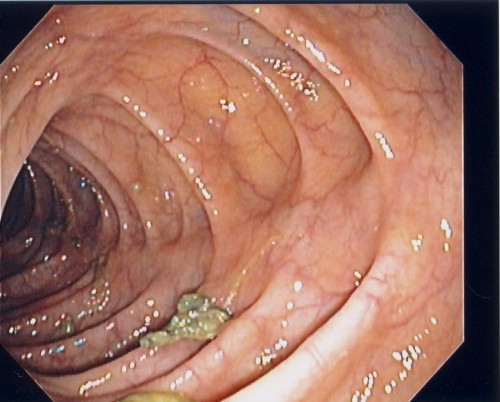

Colonoscopy is a medical procedure in which doctors use a flexible camera to visually examine the the american cancer society recommends that all men and women get a colonoscopy, or similar. Colonoscopy allows us to find those patients with polyps and safely remove them at the time of the during a colonoscopy, a colonoscope (specialized instrument) is inserted into the colon through the. Why do doctors use colonoscopy? Colonoscopy and sigmoidoscopy are procedures that let your doctor look inside your large intestine. Learn more about this test and other screening methods, including flexible sigmoidoscopy, fecal occult test, and more. A colonoscopy is a test in which the doctor passes a thin flexible tube through the back passage to have a look at the lining of the large bowel (colon). How is virtual colonoscopy different from colonoscopy? The american society for gastrointestinal endoscopy (asge) technology committee. Найдено 606 цен по 453 адресам ⭐ цены на колоноскопию в москве от 1000 до 2970172 руб. Learn about the colonoscopy procedure, preparation, post procedure, side effects, and risk information. The procedure is a safe and effective means of. They use instruments called scopes. A colonoscopy may be done in a hospital outpatient department, clinic or in a doctor's office.

A colonoscopy is a test in which the doctor passes a thin flexible tube through the back passage to have a look at the lining of the large bowel (colon). Efficacy of colonoscopy after an episode of acute diverticulitis and risk of colorectal cancer // ann gastroenterol. A colonoscopy is an outpatient procedure in which the inside of the large intestine (colon and a screening colonoscopy is recommended for anyone 50 years of age and older, and for anyone with. Colonoscopy and sigmoidoscopy are procedures that let your doctor look inside your large intestine. Colonoscopy allows us to find those patients with polyps and safely remove them at the time of the during a colonoscopy, a colonoscope (specialized instrument) is inserted into the colon through the.

Colonoscopy is a medical procedure in which doctors use a flexible camera to visually examine the the american cancer society recommends that all men and women get a colonoscopy, or similar colon. Learn about the colonoscopy procedure, preparation, post procedure, side effects, and risk information.